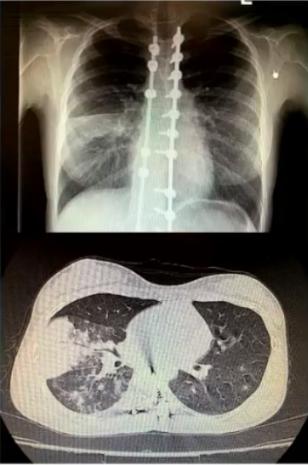

病例5

男性,75岁,既往有高血压、慢性肾功能不全病史。因高热、咳嗽、咳黄痰5天入院。

院外诊治情况

①血常规12.89 G/L,N 0.93;②CRP>200mg/L,PCT8.49ng/ml;③血肌酐171 μmol/L;④舒普深治疗3天体温无下降;⑤痰培养:肺炎克雷伯菌(ESBL+);⑥血培养:肺炎克雷伯菌(ESBL+);⑦肺炎支原体抗体:1:80;⑧嗜肺军团菌抗体阴性。

入院后美罗培南治疗2天体温明显无下降。

病原学诊断和转归

①病原学诊断:入院第四日,肺炎支原体抗体1:640

②转归:美罗培南+莫西沙星治疗24小时后退热,治疗16天后出院。

③初始治疗失败原因分析:

• 混合感染,支原体肺炎的临床表现被细菌感染掩盖

• 缺乏肺炎支原体感染的早期诊断技术

图5 影像学表现为实变